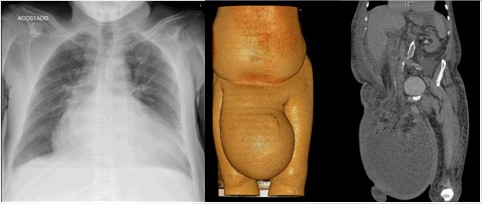

Al examen físico se palpan campos pulmonares crepitantes bilaterales en región basal, ruidos cardiacos arrítmicos sin ruidos agregados, masa inguinal gigante que sobrepasa la rodilla (40 x 29 cm aproximadamente), con áreas descamativas en región escrotal y aparente contenido líquido, poco reductible (fig.1).

Además, se realizaron otros exámenes, tales como radiografía de tórax, que mostró aumento marcado de silueta cardiaca compatible con insuficiencia cardiaca y tomografía axial computarizada de la región abdominal y miembro inferior, la cual evidenció gran masa inguinoescrotal que medía 41 x 29 cm con anillo herniario grande y aparente contenido de asas intestinales, líquido en probable relación con ascitis, así como colon ascendente (fig.2).